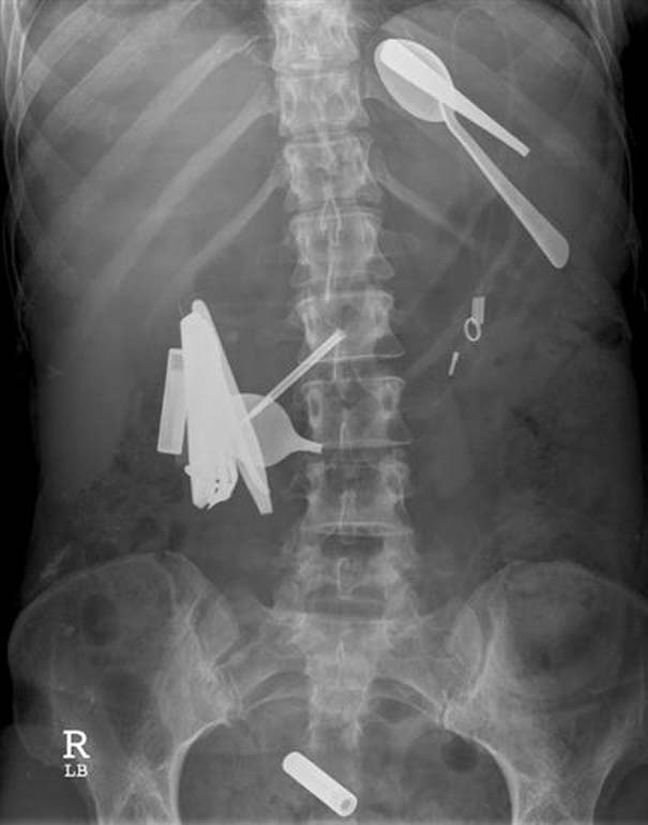

Ο,ΤΙ ΝΑ 'ΝΑΙ #φωτογραφίες Όταν μιλούν οι ακτινογραφίες! Αντικείμενα -και όχι μόνο- μέσα σε ανθρώπινα σώματα… 24·09·2013 13:33 16 σχόλια Δαχτυλίδι αρραβώνων Κλειδί Κουζινικά Χελι Μαγνητάκια Καρφιά 78 Κουτάλια και πιρούνια Φίδι